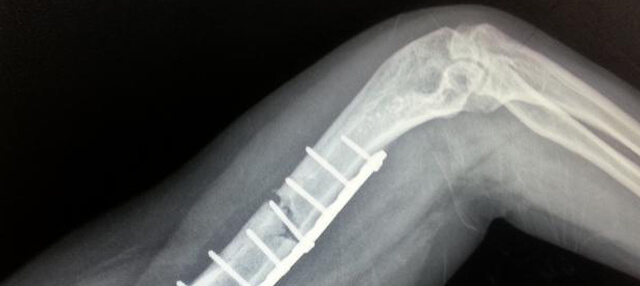

可显示关节损害或痛风石

识别痛风石影像以辅助诊断